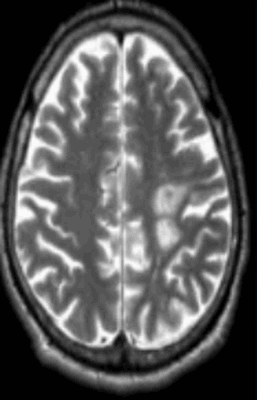

- Стадия 3 (хроническая): Гиперинтенсивная зона на Т2-ВИ (распад жиров и липопротеинов, вазогенный отек, глиоз).

- Стадия 4: Атрофия

Валлеровская дегенерация вследствие инсульта в бассейне средней мозговой артерии в левом полушарии большого мозга. Р1_А1К-изображения (а, b) и Т2-ВИ в аксиальной плоскости (с). В зоне, кровоснабжаемой левой средней мозговой артерией, визуализируется кистозный дефект с глиозом (а). Определяется повышенная интенсивность сигнала от пирамидного пути в левой ножке мозга (b) и в продолговатом мозге слева (с).